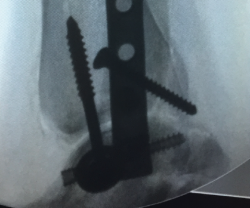

Figura 1. Fractura conminuta de la cúpula del astrágalo.

Se trata de un paciente varón de 35 años que, tras una precipitación, presenta impotencia funcional en el miembro inferior. Tras la valoración clínica y radiológica, se observa un estallido de la parte posterior de la cúpula astragalina (Figura 1).